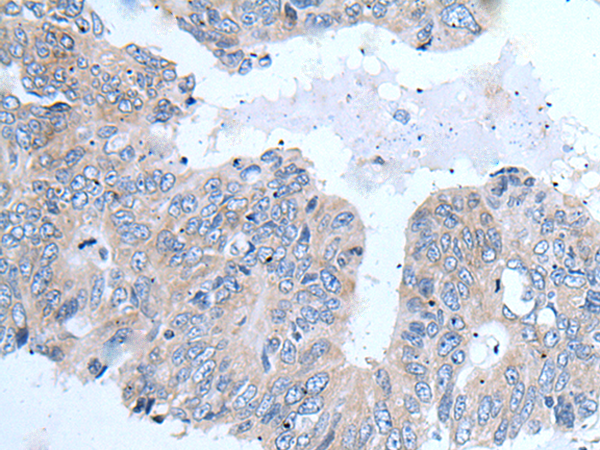

IHC positive control: |

Human lung cancer and human prostate cancer |

IHC Recommend dilution: |

25-100 |